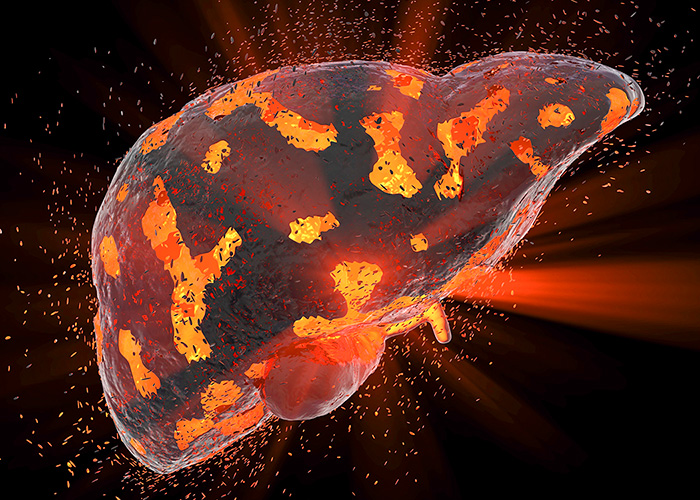

Cirrose pode levar

Silenciosa, a cirrose é uma doença crônica e progressiva que acomete o fígado, um órgão vital para o funcionamento do corpo humano. A enfermidade é um grave problema de saúde pública global e a causa de milhares de mortes anuais, gerando grandes custos para o sistema de saúde em todo o mundo. No Brasil, […]